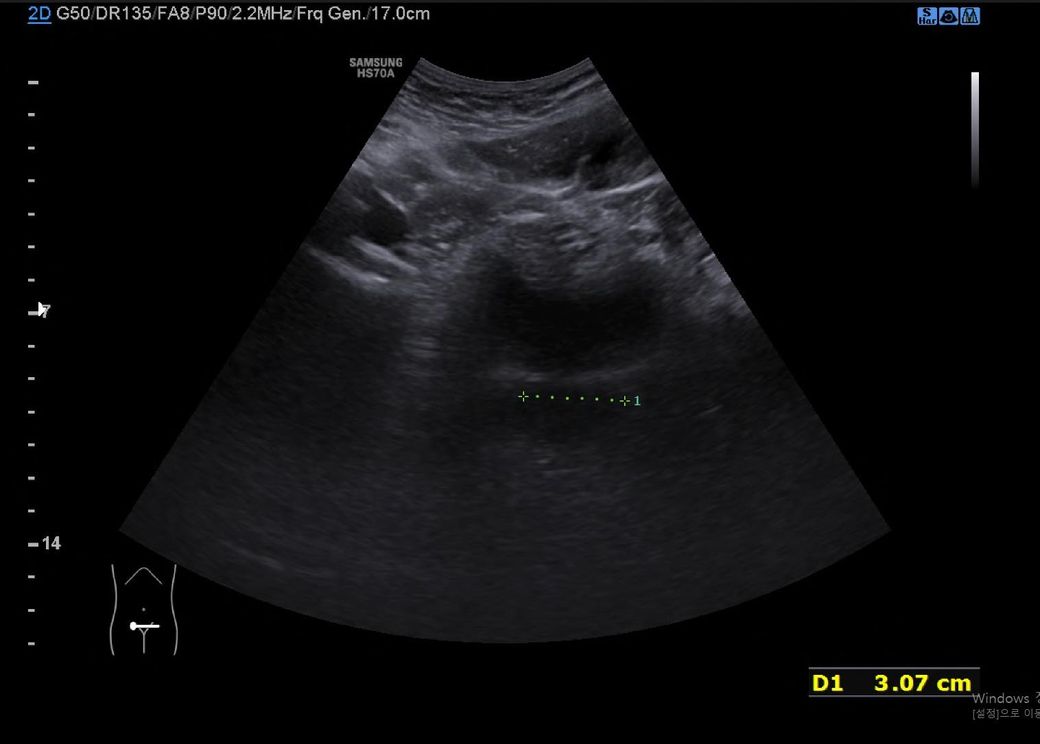

초음파사진인데 무엇인지 알려주세요.

옛날에 찍었던 초음파 사진이에요.

지방간때문에 촬영하러 갔었어요.

3cm나 되는 저건 무엇일까요?

초음파 검사가 하복부 쪽 위치에 촬영된 점 및 초음파 사진의 구조물의 생긴 모양을 보았을 때에는 방광을 촬영한 영상일 가능성이 가장 높아 보입니다.